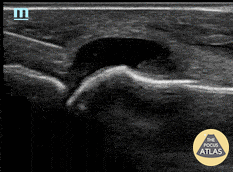

Patient with no history of crystallopathy presented with first metatarsophalangeal pain and swelling. Longitudinal view of the MTP joint revealed an anechoic effusion containing echogenic debris. Dynamic US guided aspiration was performed using an in-plane approach. Synovial fluid analysis showed monosodium urate crystals. Gram stain and fluid culture were negative. Learning point: Consider US guidance for arthrocentesis to increase success rate and maximize fluid yield especially in the case of a small effusion. Michael Cover, MD @michaelc0ver